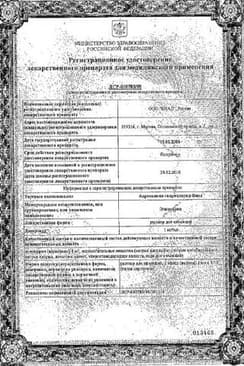

Сертификаты